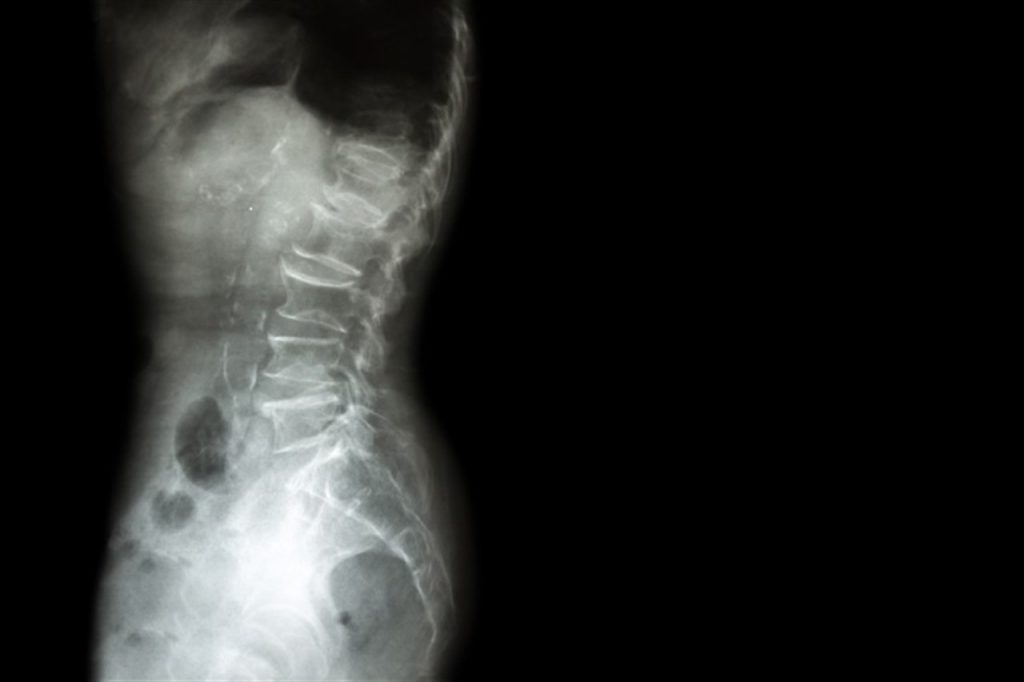

Vicky Helmlinger, fundadora de la Fundación Espolinitis Chile, inició una campaña para incluir esta enfermedad en la Ley Ricarte Soto.

Actualmente, esta enfermedad no tiene cobertura en nuestro país, con un tratamiento que cuesta más de tres sueldos mínimos y que sin tratamiento tiene consecuencias irreversibles.